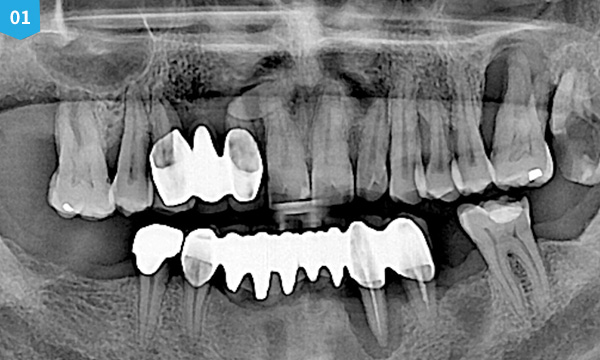

전악 임플란트는 치아가 완전히 없는 상태라도 잇몸뼈가 남아 있다면 임플란트를 여러개 심어 고정식으로 이를 해 넣을 수 있습니다. 잇몸 뼈에 단단히 고정되는 임플란트를 이용한 치료법으로 틀니를 사용할 때 보다 힘이 훨씬 좋고 내 치아 처럼 사용할 수 있습니다. 자연치아는 모두 28개 이지만 실직적으로 자연치아 개수만큼 다 심을 필요는 없습니다. 고정성 전악 임플란트를 위해서는 위 아래 턱 뼈와 맞물리게 되는 치아의 상태와 잇몸 뼈의 상태 등을 고려하여 임플란트를 식립하게 되며 보통 아래는 6~7개, 위에는 7~8개의 임플란트를 식립한 후 고정식으로 보철물을 결합하게 됩니다.

치료 케이스 보기

• before